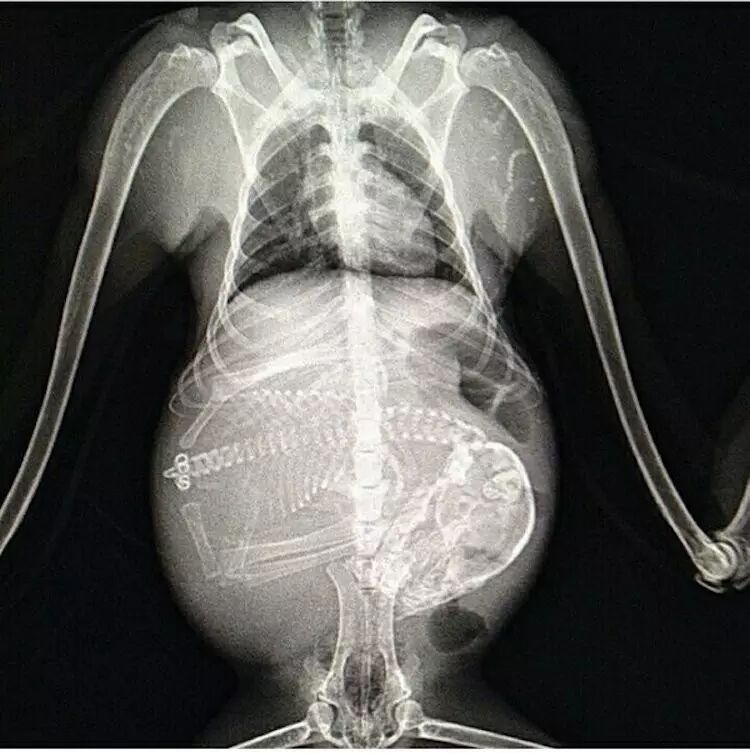

怀孕是一个非常神奇的生物现象,而这些X 光照片就更加证明到生命的奇迹让人百看不厌,从我们熟悉的猫和狗到较少见的龟、蝙蝠影像也有,大家可以看看以下,并比对和人相比的差异与相同之处。

怀孕的猫,在怀孕后约45天,小猫的骨骼就会生长得能够用 X 光拍摄到。

怀孕的狗。同样也是大概 45 天就能通过 X 光确认肚中的小狗。